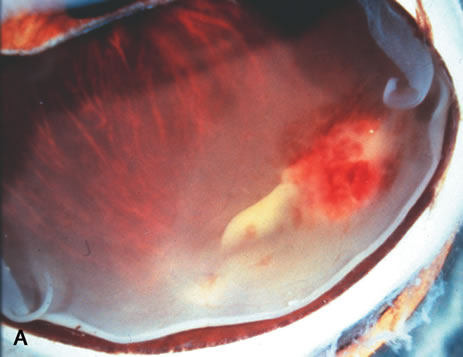

Neoplastic causes of iris nodules include melanoma, leiomyoma, leukemia, metastatic carcinoma, and retinoblastoma. Melanoma may occur as a nodular (Fig. 4A) or flat growth or as tapioca-like nodules. All these lesions show spindle shape tumor cells (Fig. 4B), or such cells may be mixed with epithelioid melanoma cells. Both spindle A and spindle B cells may be present.30 These tumors may display occasional mitotic figures, foci of necrosis, and melanophages. Iris melanomas usually are small, mainly low-grade spindle tumors and carry a relatively good prognosis when compared to ciliary body and choroidal melanomas.31–39

Fig. 4. Iris melanoma. A pigmented mass involves the iris (A), which histologically reveals spindle cells (B). (Hemotoxylin-eosin ×60.)